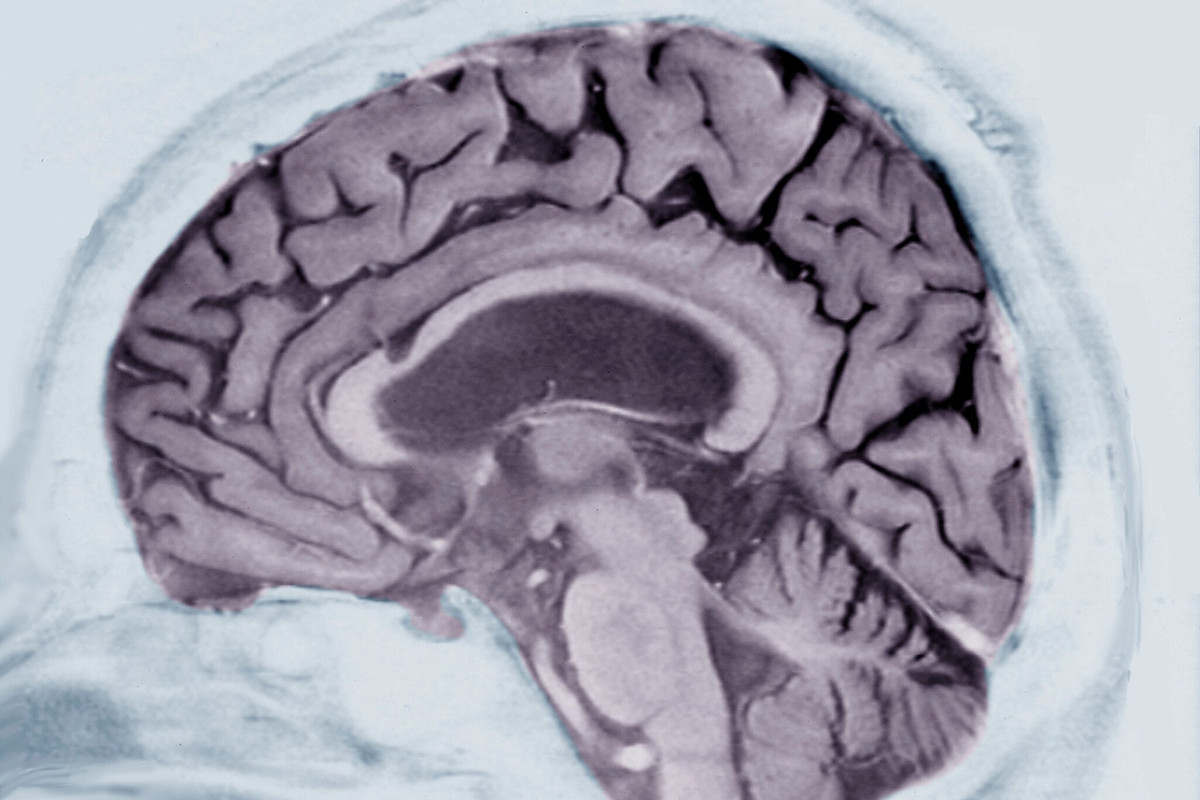

সমীক্ষা অনুসারে, রোগের লক্ষণগুলি দেখতে এমআরআই ইমেজিং এবং জ্ঞানীয় পরীক্ষার মতো অন্যান্য পরীক্ষাগুলিও করা হয়েছিল। এই গবেষণায় আবিষ্কারের মূল বিষয় ছিল যে গবেষণায় অন্যান্য পরিচিত রোগ-সম্পর্কিত রক্ত-ভিত্তিক বায়োমার্কারগুলির বিশ্লেষণের আগে GFAP নামক একটি নির্দিষ্ট প্রোটিনের মাত্রা বৃদ্ধি পেয়েছে। এই বৃদ্ধি আলঝেইমার রোগের লক্ষণ শুরু হওয়ার ১০ বছর আগে শুরু হয়েছিল। ব্যাখ্যা করুন যে GFAP হল একটি প্রোটিন যা মস্তিষ্কের অ্যাস্ট্রোসাইট দ্বারা নির্গত হয়। এগুলি বিশেষ কোষ, যা অন্যান্য ফাংশনের সঙ্গে মস্তিষ্কের ইমিউন সিস্টেমে অংশ নেয়। গবেষণা আরও দেখায় যে জিএফএপি মাত্রা এমন লোকেদের মধ্যে উচ্চতর যাদের কোনও জেনেটিক কারণ ছাড়াই প্রাক-ক্লিনিক্যাল অ্যালঝাইমার রোগ রয়েছে।